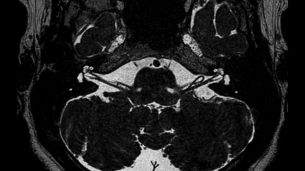

Dzięki wysokiej czułości SWIp zwiększa kontrast krwi odtlenowanej (żylnej) lub złogów wapnia, a w połączeniu z innymi danymi klinicznymi może pomóc w diagnostyce różnych zaburzeń neurologicznych. SWIp zapewnia zależne od podatności magnetycznej obrazowanie 3D mózgu w wysokiej rozdzielczości, które można z łatwością włączyć w standardową praktykę szpitala.